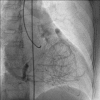

ALCAPA syndrome (anomalous origin of the left coronary artery from the pulmonary artery) is an exceedingly rare disease but lethal with clinical expression from myocardial infarction, congestive heart failure to death during early infancy and rare survival to adulthood. A 75-year-old woman with ALCAPA syndrome presented with angina (Canadian Cardiovascular Society functional class II) over past 8 months. Physical examination was within normal limits except pan-systolic murmur at the apex. Electrocardiography displayed poor R progression in precordial leads and signs of left ventricular hypertrophy. Echocardiography established presence of continuous flow entering the pulmonary trunk and normal systolic function. Coronary angiogram showed absence of left coronary artery originating from aorta, dilated and tortuous right coronary artery (RCA) and abundant Rentrop grade 3 intercoronary collateral communicating with left coronary artery originating from pulmonary trunk which was also confirmed on CT angiogram thus establishing diagnosis of ALCAPA. Survival in eight decade with this anomaly is still an enigma.